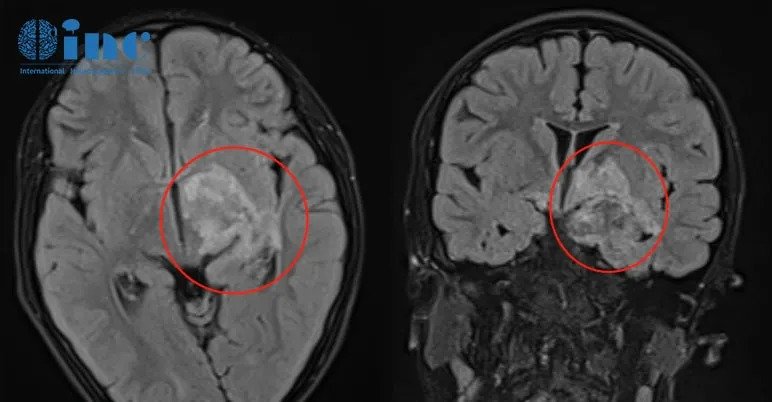

MRI显示肿瘤已延伸并浸润基底节和丘脑

半年内该残留增加了2-3毫米,医院建议再次手术,但丘脑,基底节和大脑脚部分仍是手术风险大,无法切除。而且医生还说要把孩子的颞叶切了,杨女士慌了。没想到原本良性的肿瘤,现在却面临着2次开颅……